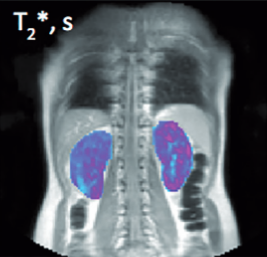

From study design to final reporting, Bioxydyn delivers repeatable MRI biomarkers that reveal tissue function, physiology and change. Our operational excellence and metrology help you compare results across sites, scanners and timepoints.

Disease areas and services supporting quantitative MRI biomarkers across clinical trials.